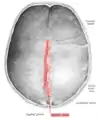

![]() Human adult skull from above. Sagittal suture labeled at center. | |

Animation. Sagittal suture shown in red.